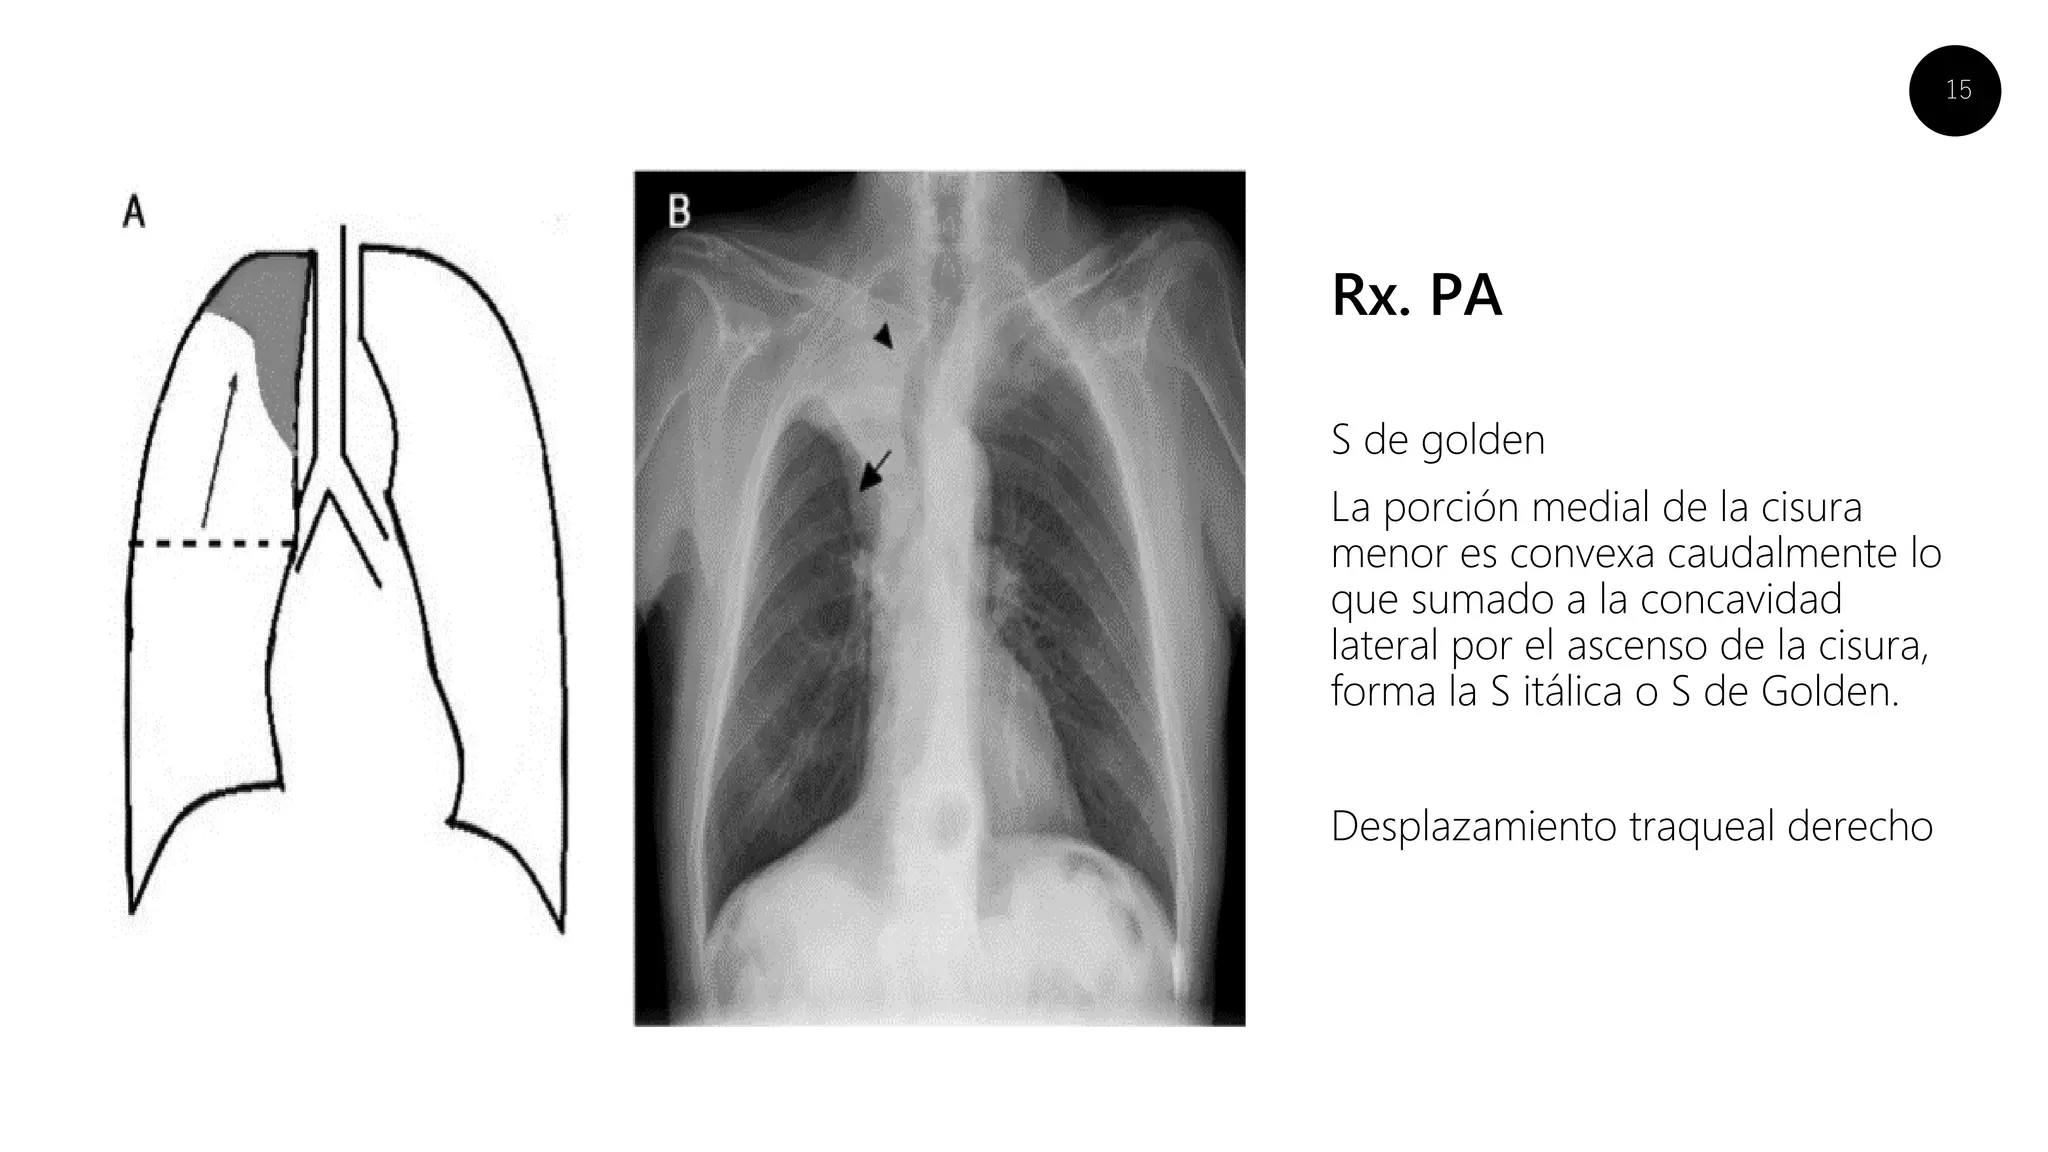

Rx. PA

S de golden

La porción medial de la cisura

menor es convexa caudalmente lo

que sumado a la concavidad

lateral por el ascenso de la cisura,

forma la S itálica o S de Golden.

Desplazamiento traqueal derecho